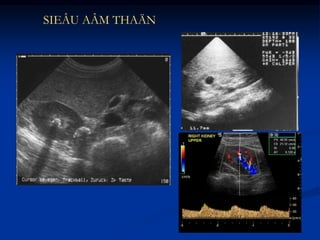

SIEÂU AÂM THAÄN

 Chỉ định: NTT tái phát thường xuyên ở nữ

NTT có biến chứng, NTT lần đầu tiên ở

nam trẻ

 Xét nghiệm hình ảnh:

 Siêu âm bụng

 Chụp hệ niệu có cản quang: UIV

 Nội soi bàng quang

 Chụp bàng quang có thuốc cản quang